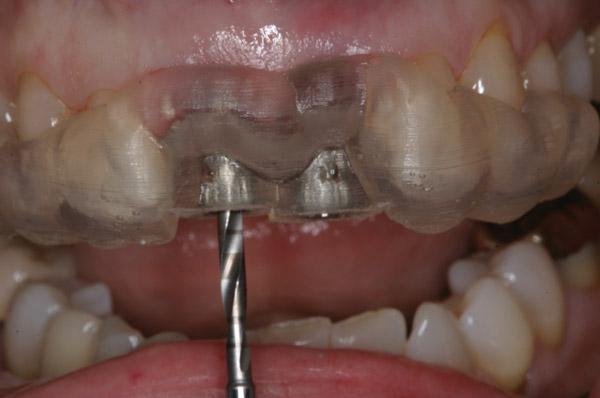

Figure 6  CT-derived fabrication of a surgical guide enabled proper fixture placement into the fresh extraction sockets.

Figure 6